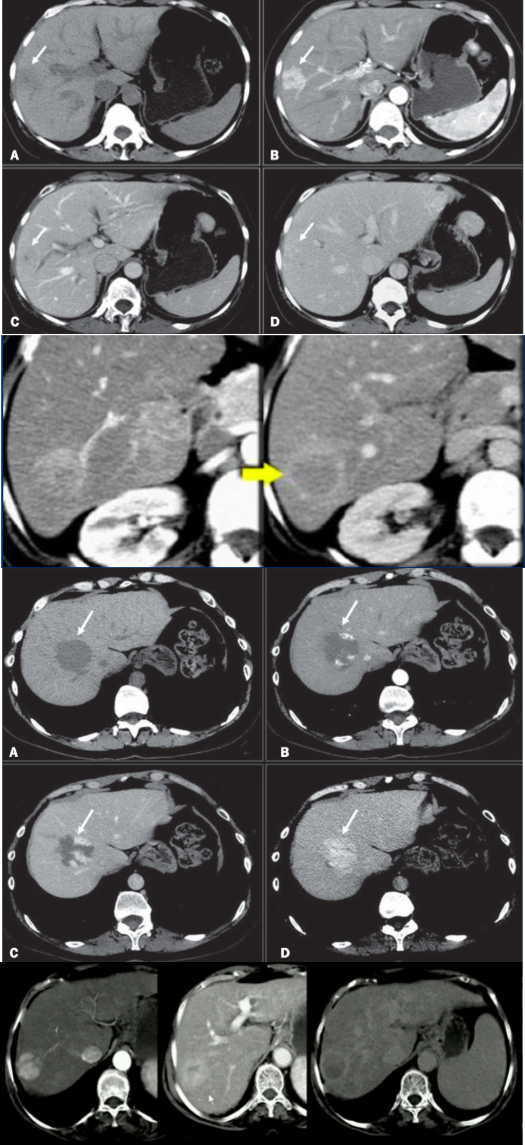

Tumores hepáticos e seus respectivos quadros clínicos e achados tomográficos (4)

A

1. Hemangioma: dor em hipocôndrio D/ assintomático; enchimento periférico globuliforme e contraste persiste na fase portal

2. Adenoma hepático: uso de ACO; nódulo bem delimitado, hiperecóico, com washout em fase portal e deixa um halo hipertenso (cirurgia se sintomático ou > 5cm ou desejo gestacional ou em homens). Caso rompa, e paciente estável, fazer angioembolização hepática

3. Hiperplasia nodular focal: pode estar tmb relacionado ao uso de ACO, mas menos que o adenoma; temos uma cicatriz central no nódulo

4. carcinoma hepatocelular: fatores de risco (hepatite, cirrose) + nódulo com washout

1-HNF, 2-adenoma, 3-hemangioma, 4-CHC